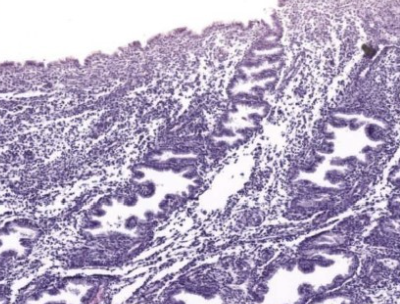

label this slide

cervix

transformation zone (to stratified squamous non keratinized epithelium)